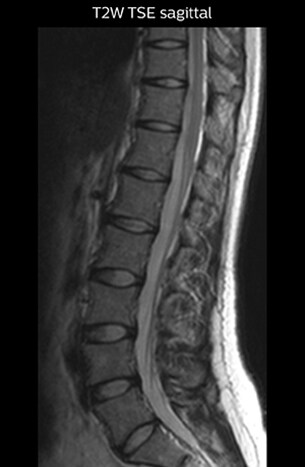

“For example, in sagittal images, when the presence of fat is observed in the intervertebral foramen, it suggests that there is a margin around the nerve. Similarly, the absence of fat indicates that the nerve is being compressed. So, we used to deduce nerve compression indirectly. With NerveVIEW, however, we can observe the condition of the nerves directly, regardless of the presence or absence of fat. We always prefer such direct observation of anatomy over having to make an inference about it.”

T2W sagittal and axial